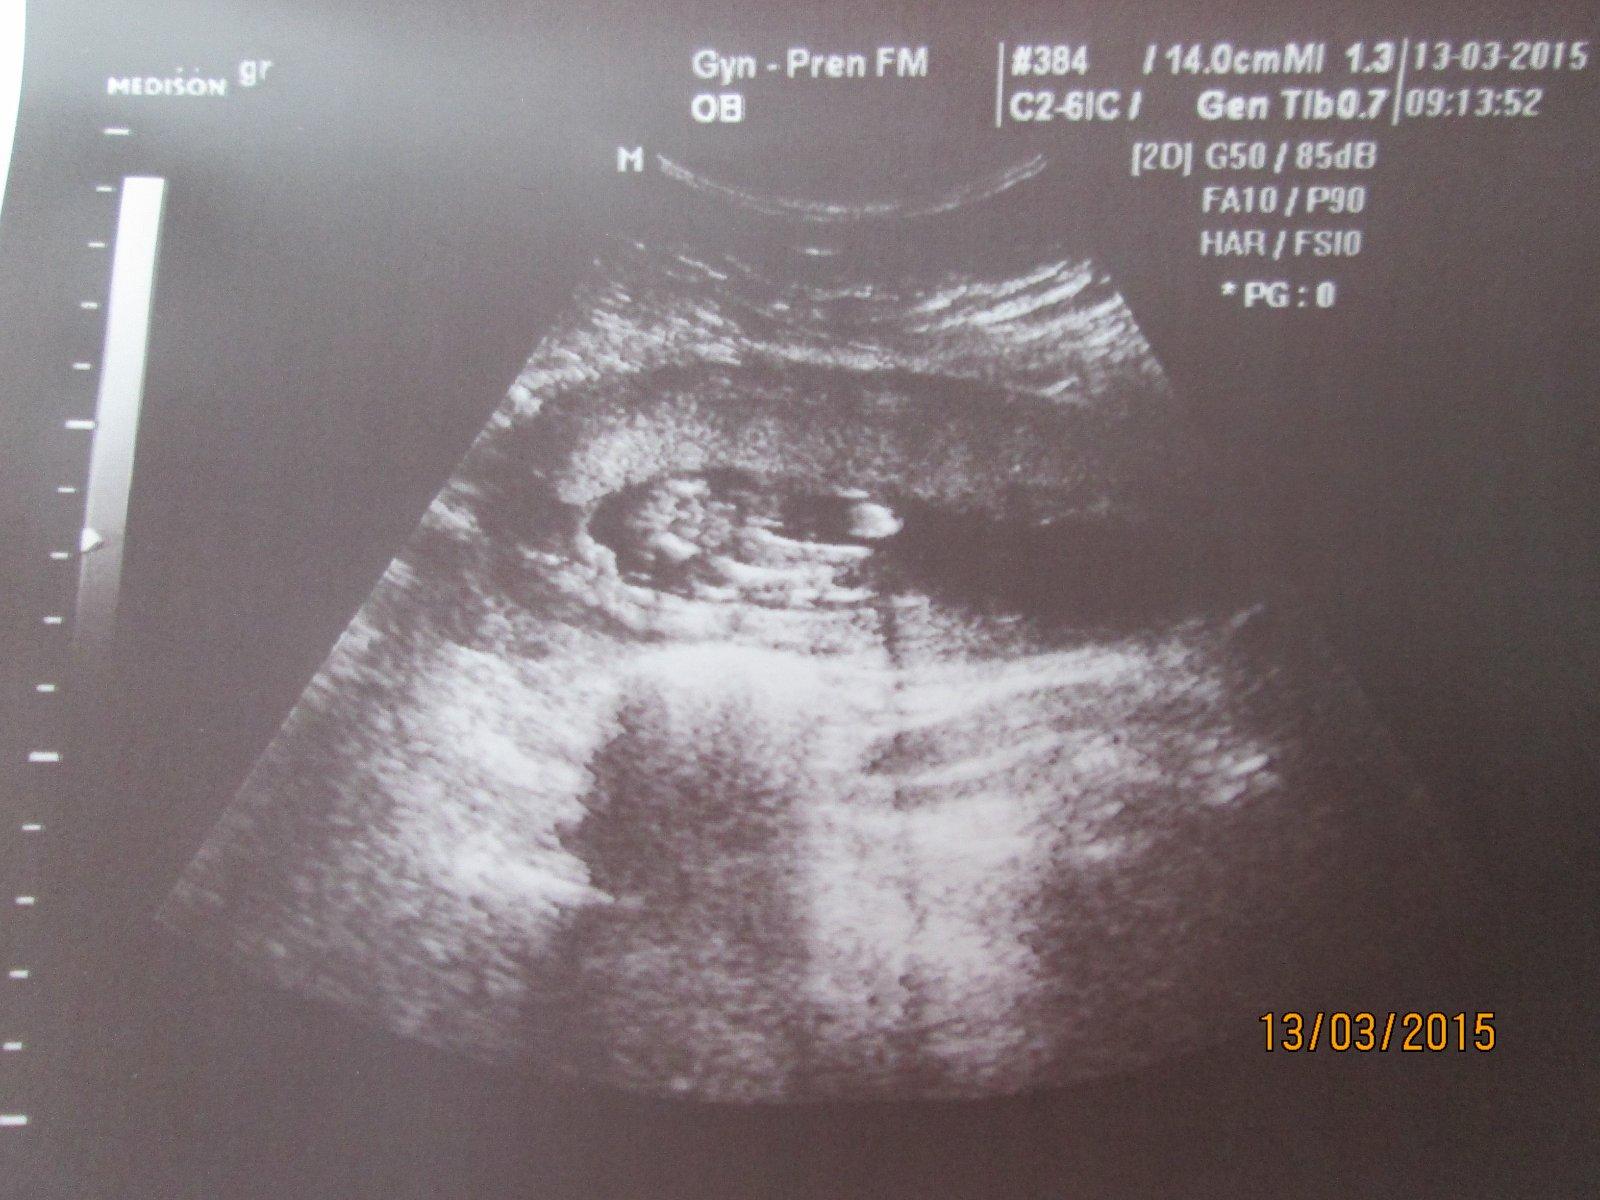

Ahoj holky.Dnes kontrola u dr. jsem 16 tt.Vyfotila mi rozkrok,ale já se v tom nevyzdám.Nevím ani kde jsou nohy natož kde má být údajně pohlaví.Je tu nějaký odborník který to pozná? 🙂 Dr. mě napíná a prý nechá na jiném dr. ať mi řekne co to bude.Kontrola ale až za měsíc 😒

@jarmulka Nevyznáš se v tom prosím ty? 😒 Obě fotky jsou stejné,jen ta druhá je zvětšenina

A můžete mi prosím holky některá z vás nějak zakroužkovat,kde mám hledat?Já fakt ani nemám ponětí 😀

Holky,kde tam vidite pindoura s kulkama?ja se tady snazim stahnout aplikaci do telefonu,abych mohla fotku oznacit a furt nemuzu nic najit ☹ chtela bych oznacit to kavove zrno,ktere vidim 😀

@anetka1701 no tak tam presne vidim kavove zrno 😀

Akorat jsem na telefonu a nemuzu to zakrouzkovat,nemuzu najit aplikaci,abych mohla kreslit do fotky 😁

@emily2015 kávová zrna jsem viděla zatím naživo dvě a nějak to vypadalo prostě jinak než tohle... :oD

@anetka1701 ja jsem zase videla na utz pytlik s kulkama a take to vypada naprosto jinak 😀